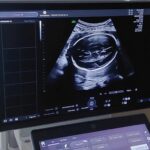

Kobiety w ciąży od 1 kwietnia mogą wykonać badania prenatalne w Klinicznym Szpitalu Wojewódzkim nr 2 w Rzeszowie.

Badanie refunduje NFZ, a pozwala ono na wczesne wykrycie wad płodu i rozpoczęcie leczenia jeszcze w łonie matki

Badanie prenatalne jest bezinwazyjną metodą, aby skorzystać z bezpłatnych badań wystarczy mieć skierowanie od lekarza prowadzącego ciąże. Można umówić się telefonicznie dzwoniąc do poradni położniczo – ginekologicznej szpitala.